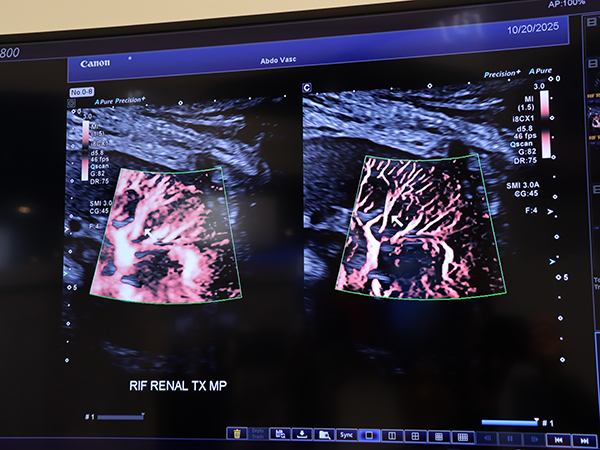

一方,SMI Angio modeは,キヤノンメディカルシステムズがこれまで磨きをかけてきた微小血管・低流速の血流を可視化する独自技術Superb Micro-vascular Imaging(SMI)を進化させ,微細血管のより明瞭な描出を実現した。従来から注力して開発してきた周波数領域の分析や信号の抽出に加え,時間方向に信号を解析してドプラ信号に揺らぎを生じさせるノイズ成分を除去することで,いっそうクリアな血流像を描出できるようになっている。微細な部分のノイズが抑制されることで血管の分岐も明瞭化し,肝臓や腎臓,乳腺,甲状腺などでの描出能向上が期待される。研究向きの機能であり,現在,米国や日本で検討が進められている。

「SMI Angio mode」(右)では従来のSMI(左)よりも微細血管を明瞭に描出